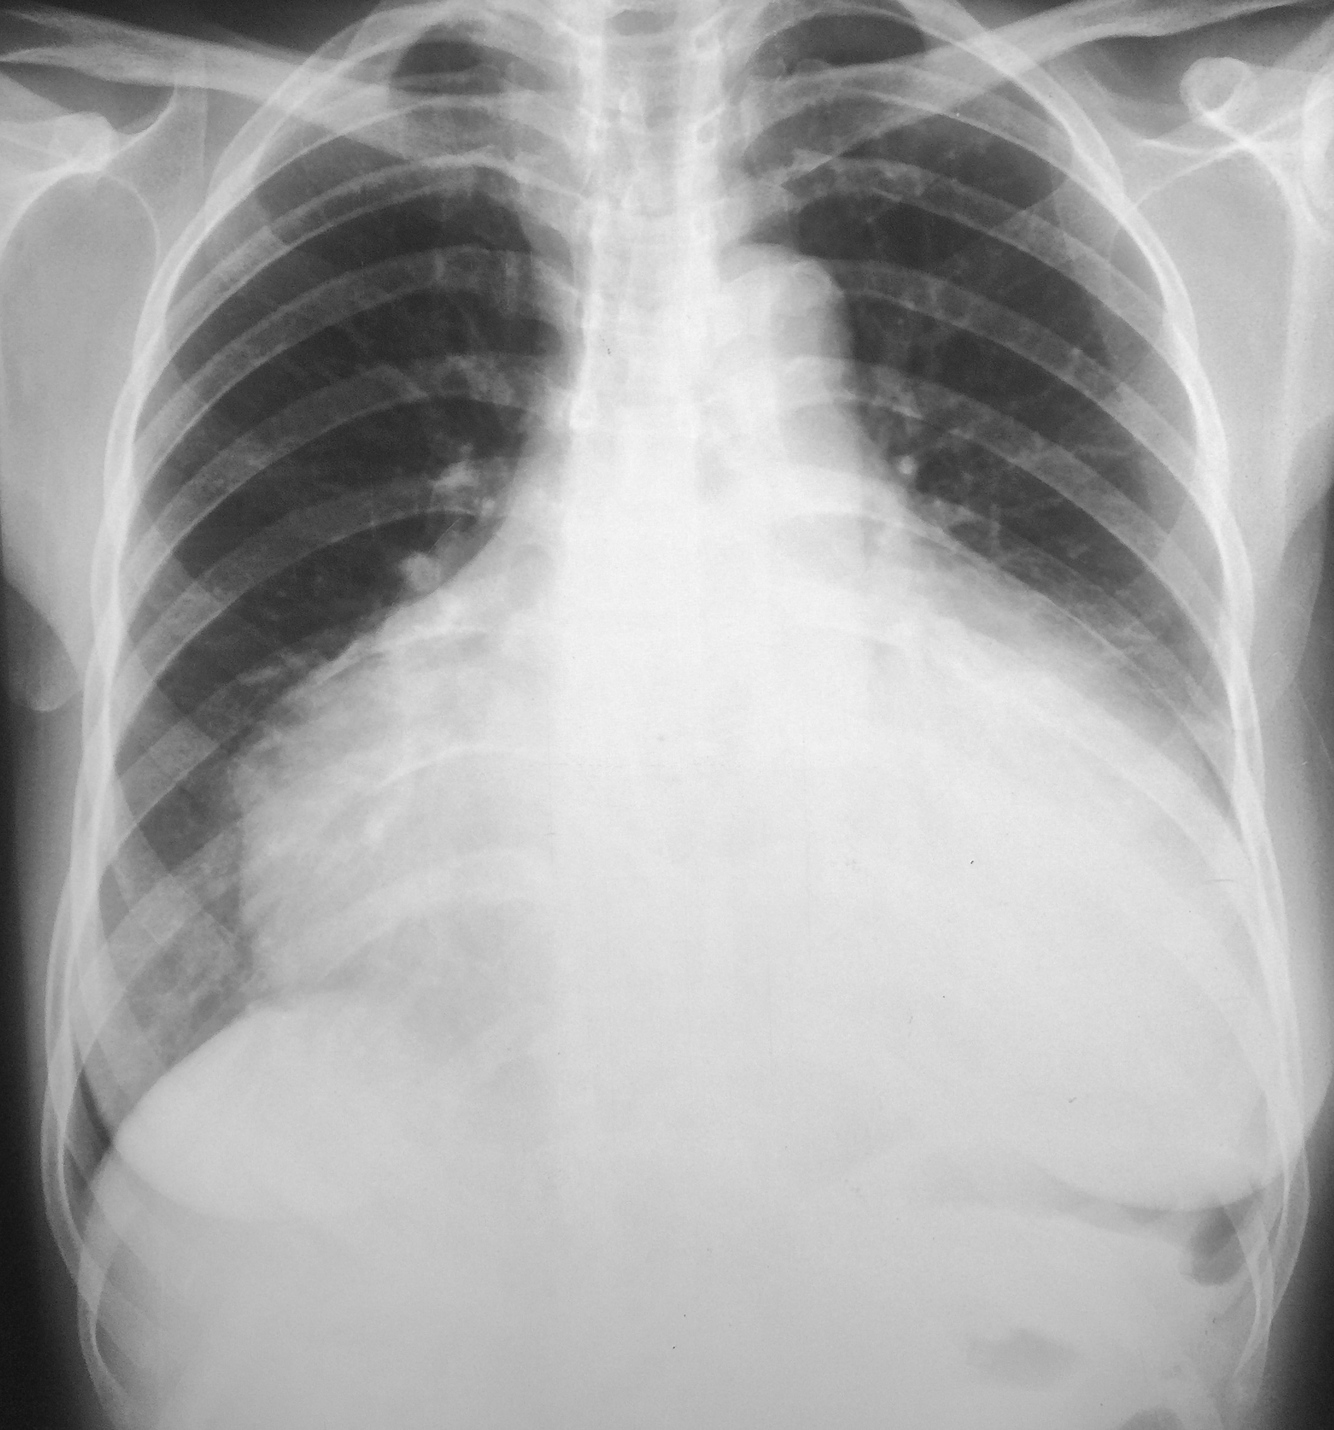

67-year-old male with history of prosthetic aortic valve stenosis, now with dyspnea on exertion and lower extremity swelling

Vertical retrosternal opaque stripes representative of possible pericardial effusion (“oreo cookie sign”).